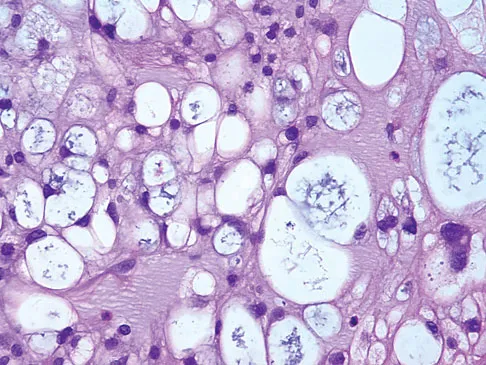

A 35-year-old man reports the development of a painful 2-cm nodule on his dorsal wrist over the past 3 years. A surgeon excised the lesion with a presumptive diagnosis of a ganglion cyst. Histology sections from the excision are shown in Figures 11a and 11b. What is the most likely diagnosis?

Explanation